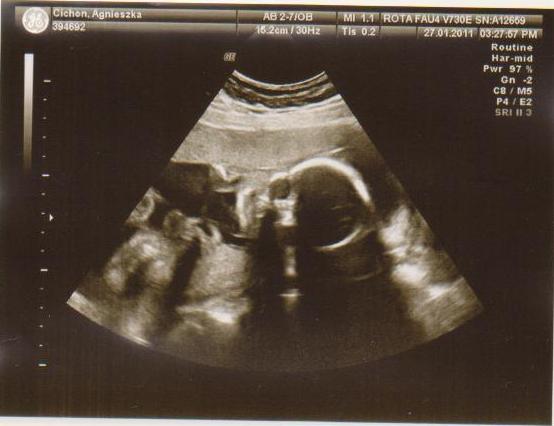

cześć dziewczyny to i ja chciałabym do Was dołączyć, właśnie znalazłam to forum. Mieszkam w Irlandii od 4 lat i mam synka 21 miesięcy, a teraz jestem w 28 tc bliźniaczej :-) dwie dziewczynki dwujajowe :-) też mnie trochę przeraża poród bliźniaków ale trzeba jakoś urodzić ;-) Pierwszy poród miałam jak marzenie szybko, sprawnie i nawet bez znieczulenia, mam nadzieję że i tym razem bęzie podobnie.

Hej podwojne mamunie:-)Ja juz rozpakowana dawno mamusia dubeltowka.Gratuluje wam serdecznie i witam w gronie tych wybranych hihiNiczego sie nie bojcie.Ciaxa blizniacza jest pod specjalna opieka.Czekaja was czeste wizyty w szpitalu i czeste ogladanie maluszkow na usg :-)

wklejam tylko zdjecia Mateuszka Tichonka na jej prośbe :-)

9a.jpg3a.JPG4a.JPG5a.jpg8a.JPG2a.JPG6a.jpg7a.JPG1a.jpg